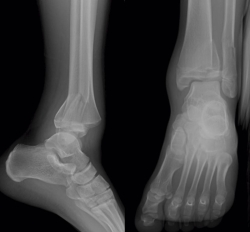

Se trata de un varón de 13 años de edad que acude a urgencias tras sufrir una caída y con eversión forzada del tobillo jugando al fútbol. A la exploración, presentaba inflamación en todo el tobillo izquierdo (región anterior y ambos maléolos) sin déficit neurovascular. En la radiografía simple se observó una fractura epifisiolisis de tipo IV (Figura 1).

Figura 1. Radiografía: epifisiolisis de tipo IV asociada a fractura de tercio distal de peroné.